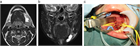

1. 頸部嚢胞性疾患は、先天性と後天性に区分される。先天性疾患は、小児・若年者の疾患であり、発生に沿った局所部位に波動を伴う腫瘤として確認される。これらの病態の理解には発生学の知識が必要になる。また、実際に臨床上の「嚢胞性」のなかに、画像上は充実性にみえる場合(蛋白濃度が高い内容液や血液を含む嚢胞)や、充実性腫瘍(脂肪腫は柔らかいため嚢胞性腫瘤の理学的所見を呈している)も含まれる。ただ、一般的に嚢胞とは分泌物が袋状に貯まる病態を指す( G)。

1. 頭頸部画像診断上、位置、形状、大きさ、壁の性状、境界、隔壁の有無、充実性部分や石灰化の有無、発生部位と進展範囲などが評価される。